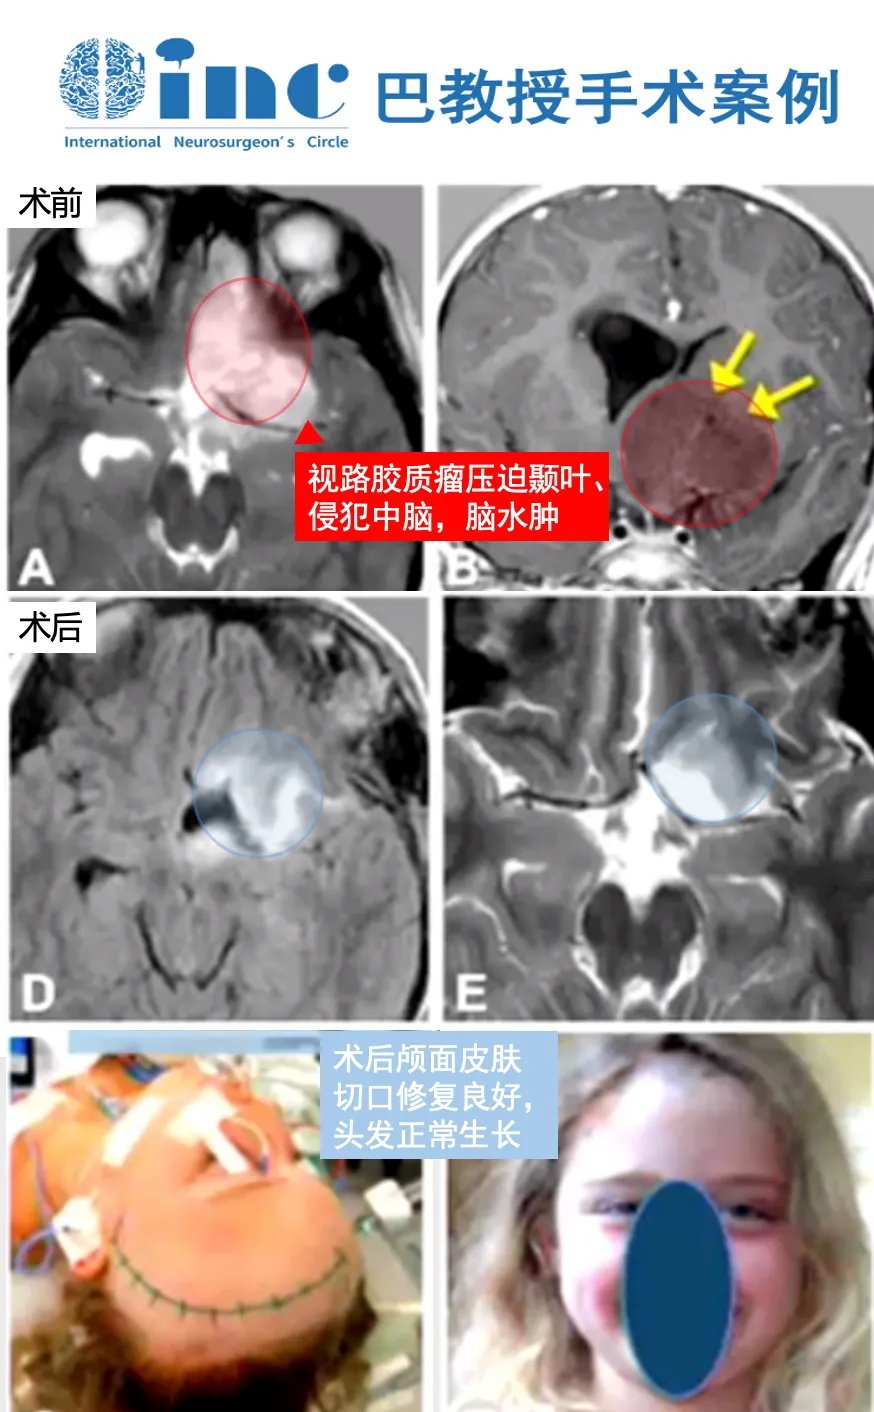

8岁女孩-视路下丘脑胶质瘤

8岁女孩,大型视路-下丘脑胶质瘤(箭头),弥漫性,浸润了左侧的中脑(A、B)。患者头痛和疲劳,没有神经缺损。手术切口(C)。组织病理学检查显示星形细胞瘤。最初实现了部分肿瘤切除,随后,患者接受了放射治疗,8个月后MRI显示残留肿瘤体积进一步减小(D,E)。无手术并发症,无额外的神经、认知或内分泌疾病发生(F)。